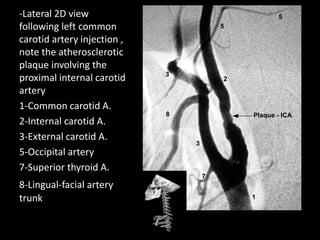

-Lateral 2D view

following left common

carotid artery injection ,

note the atherosclerotic

plaque involving the

proximal internal carotid

artery

1-Common carotid A.

2-Internal carotid A.

3-External carotid A.

5-Occipital artery

7-Superior thyroid A.

8-Lingual-facial artery

trunk